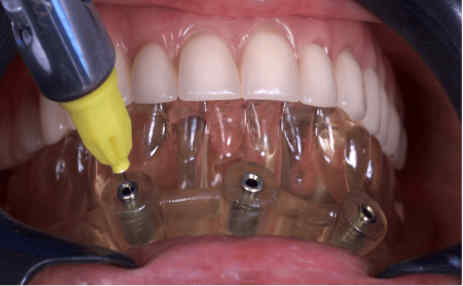

The provisional prosthesis was directly relined and secured using titanium abutments and flowable resin (Figures 9, 10). The installation of the temporary prosthesis for immediate loading was performed (Figure 11). The final panoramic radiograph and tomography image showing the result was obtained, revealing the implant placement with immediate provisional fixed rehabilitation (Figures 12, 13).

FIGURE 9: Fitting the temporary prosthesis into the base of the guide

FIGURE 10: Capture of the prosthesis with flow resin and closure of spaces outside the mouth*

*Coifa for Mini-conics Implacil – Osstem